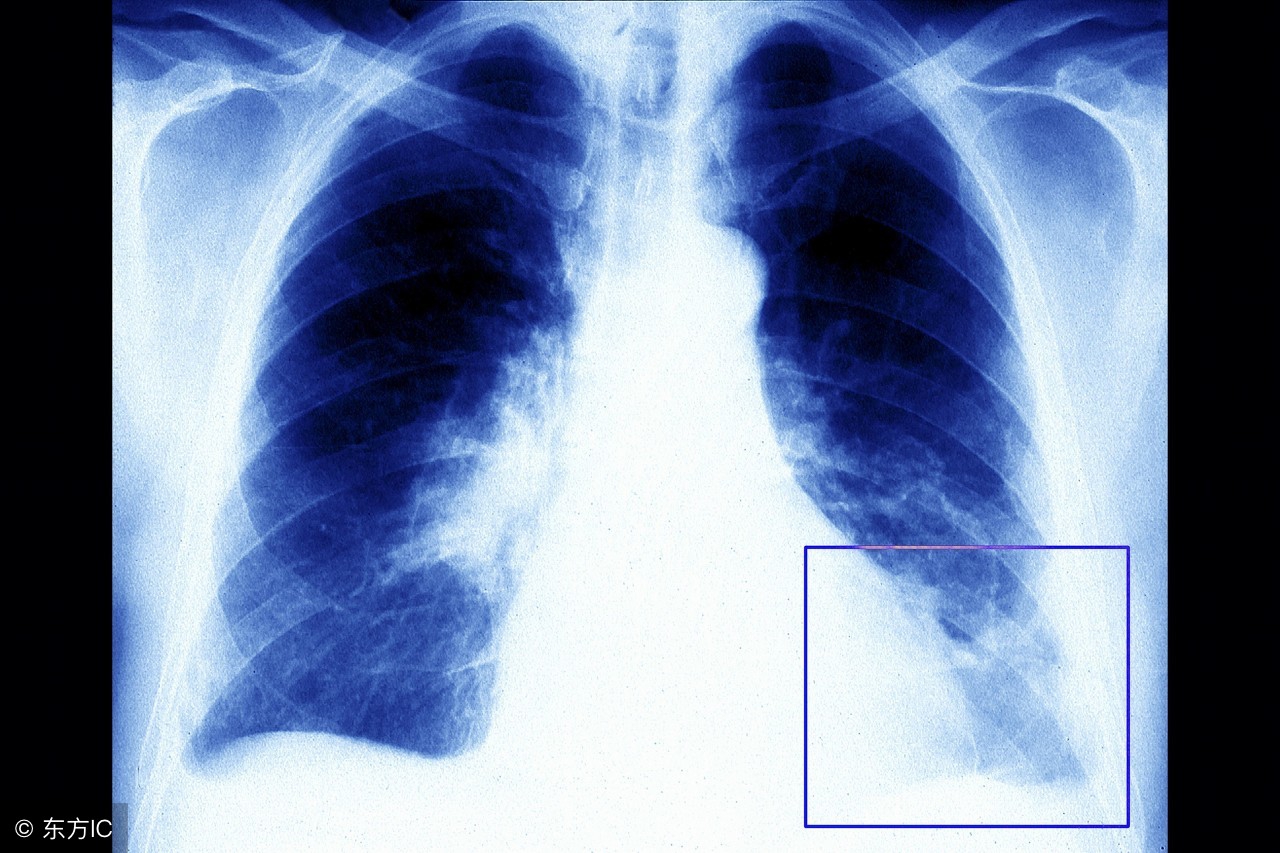

注:文中图片来自网络,如有侵权请联系删除